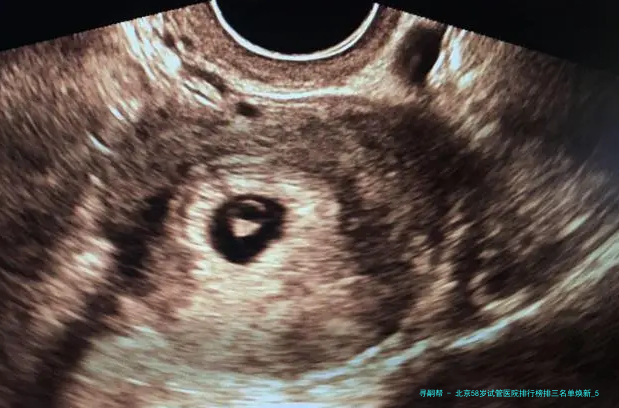

“医生,我58岁AMH值几乎为零,仍旧有可能用自己的卵子做试管吗?”在北京某生殖中心咨询室,一位鬓脚花白的女士紧握化验单的手悄悄发抖——这便是很多超高龄家庭求子路的真实缩影💔。58岁生育堪称“逆天改命”🧬:卵巢功效彻底衰竭、胚胎染色体不同寻常率超80、妊娠并发症风险迅猛上涨……选错医院不仅人财两空,更可能错失后的生育机会!2025年北京具备试管资质的医院达18家,但真实擅长超高龄方案的仅寥寥数家。本文结合新临床数据,揭晓严选前三医院排行、反转策略与性价比方案,让每一分盼望都用在刀刃上!

58岁试管成功的重要在于医院是否拥有个别化促排方案、胚胎基因学筛查(PGT)技术、多科目并发症处理能力。根据2025年北京市辅助生殖质量报告,下面列举三家医院在超高龄领域表现突出(按技术储备、临床数据、患者口碑综合排序):

答:核心差异在于胚胎质量、子宫容受性、个体化方案三重因素。2025年份限制据表现,58岁病患胚胎染色体异常率超85,但通过三代试管PGT筛查可以筛选除90异常胚胎,将临床妊娠率从5提升高到15以上。